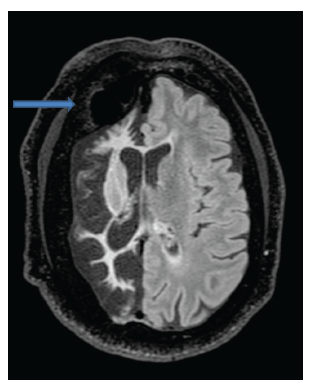

En los estudios complementarios, el paciente cuenta con electroencefalograma que evidencia actividad epileptiforme focal a derecha y episodios motores paroxísticos no epilépticos, y resonancia magnética de cráneo con protocolo de epilepsia (secuencias T2 coronal, FLAIR axial y T1 axial) que muestra una extensa disminución volumétrica en todo el hemisferio cerebral derecho, que se asocia a gliosis cortical y subcortical. Además, también se observó un engrosamiento compensatorio de la calota craneana y un aumento del tamaño del hemiseno frontal (figuras 1, 2 y 3).

FLAIR axial

Figura 2: FLAIR axial

Fuente: los autores con base en la historia clínica.